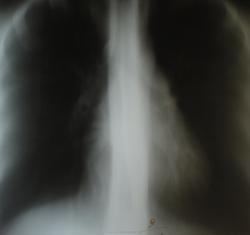

От фтизиатра к рентгенологу? Это что-то новое На обзорном снимке или группа очагов, или инфильтрат с распадом. В срезах не видно... Еще укладка вся кривая, вертелся наверное пациент

На обзорном снимке или группа очагов, или инфильтрат с распадом. В срезах не видно... Еще укладка вся кривая, вертелся наверное пациент

Нет. Просто томограммы "пережаренные", верхушки срезаны. Лаборанту необходимо сделать строгое внушение.

В проекции переднего отрезка 2 ребра слева

не вижу ничего. сколиоз, поворот.